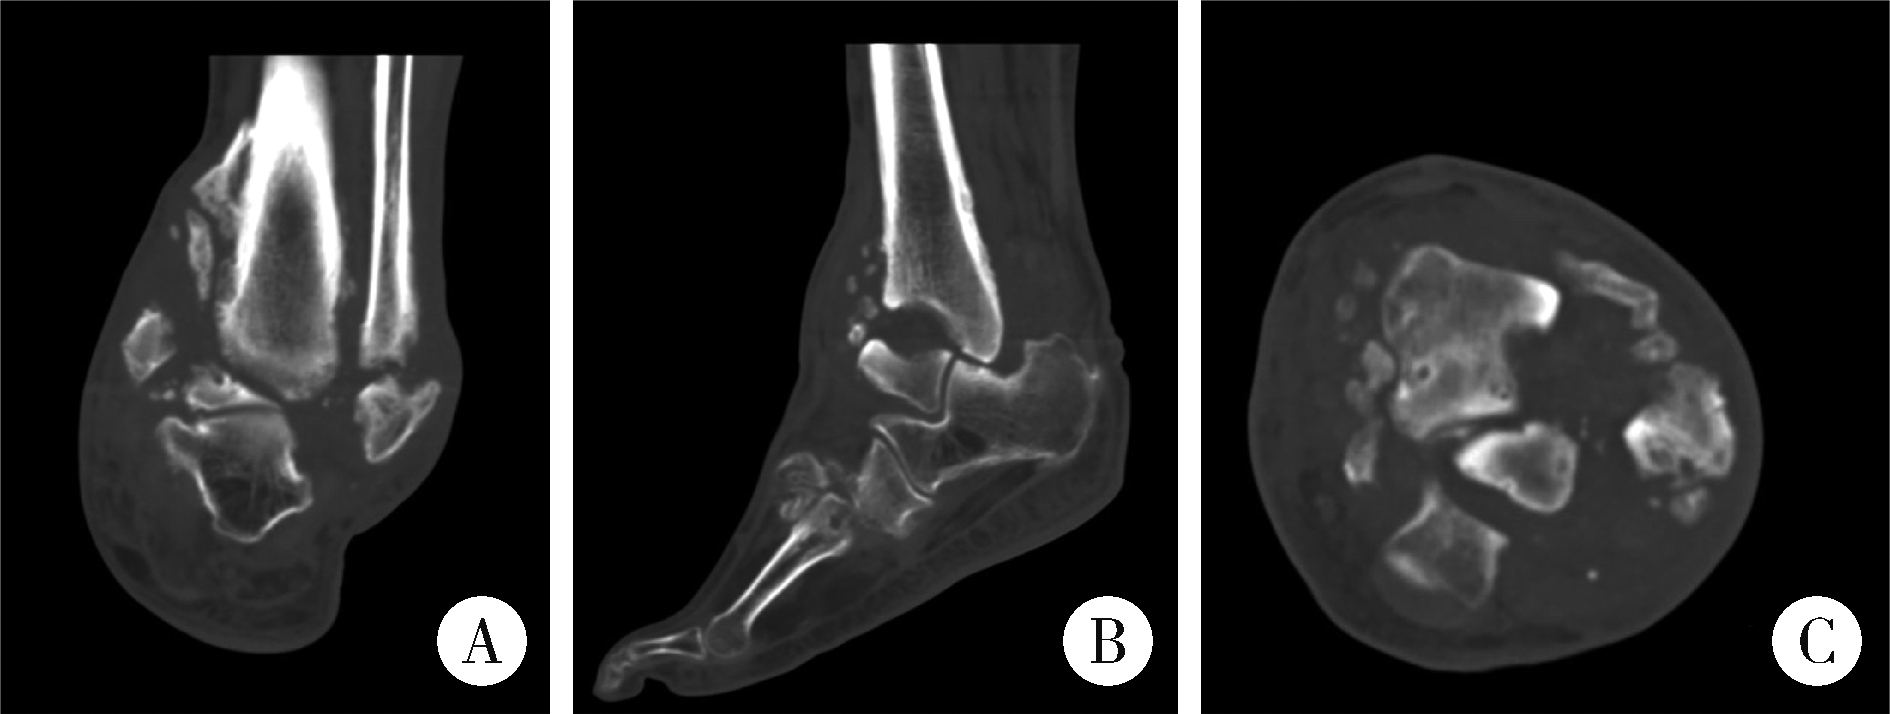

Figure 3

Computed tomography image of the left ankle A, coronal plane; B, sagittal plane; C, axial plane. Computed tomography reveals extensive osteolysis, sclerotic changes, and severe joint destruction of the left ankle."